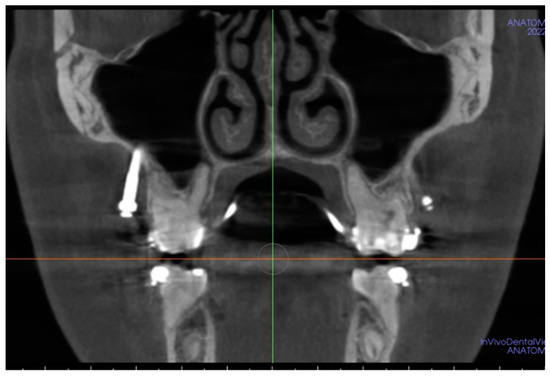

Considering the practical implications of the abovementioned research, it can be stated that in Polish patients, the mean bone depth at the area of infrazygomatic ridge rarely reaches a minimum recommended value of 6 mm. Surprisingly, our clinical experience indicates a relatively good incidence of IZC mini-screws survival, even in the absence of bone of sufficient thickness (Figure 7 presents a CBCT scan of IZC mini-screw application in the case of small bone depth).

Figure 7. IZC mini-screw with an insertion depth of 1.5 mm, successfully used for the dystalization in the upper arch.